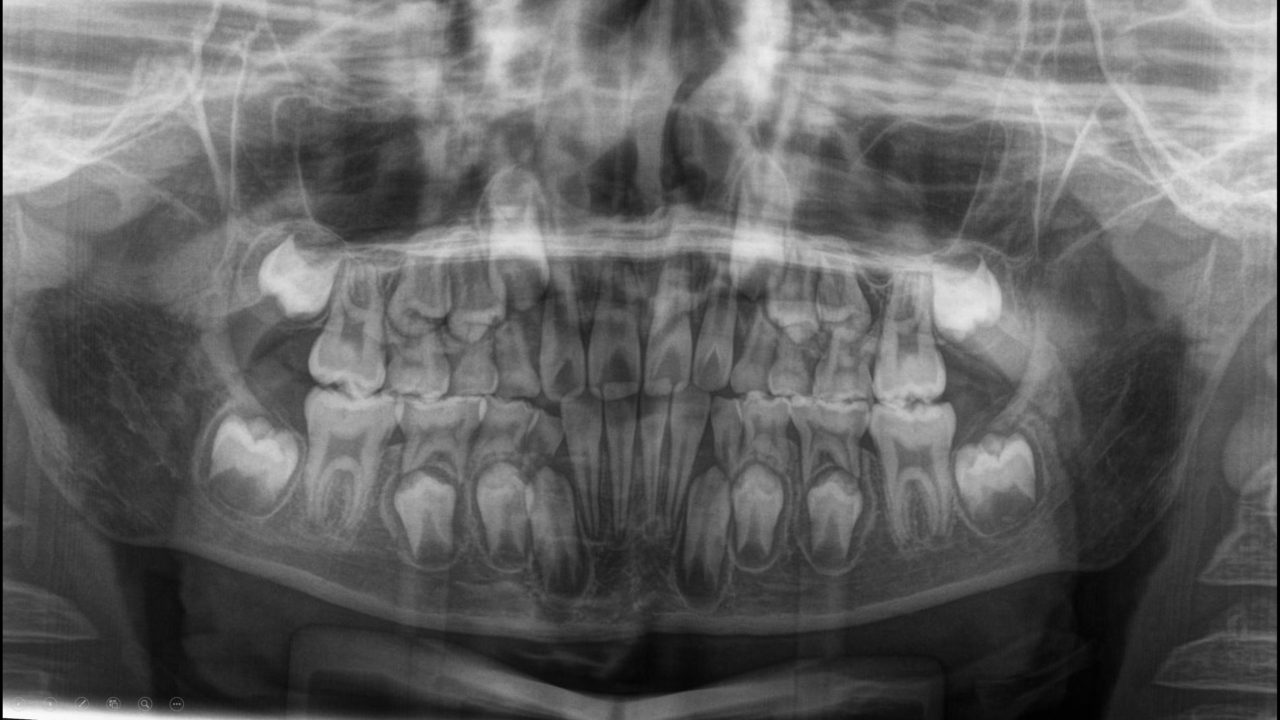

治療後レントゲン

側方歯のスペースは確保されている。